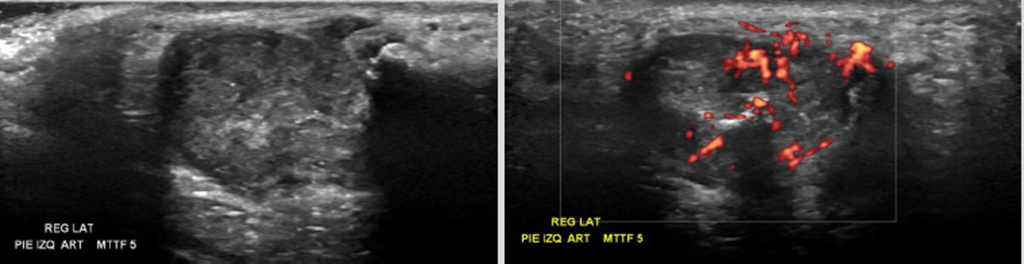

• Diagnóstico/hipótesis: Sinovitis y tenosinovitis del 5to ortejo

• Sintomatología: Paciente de 42 años, refiere dolor en región de la articulación MTTF 5to ortejo de larga data, con aumento de volumen y sensibilidad la paso del Transductor.

• Distensión de la vaina de los Td. Peroneos, con eco estructura heterogénea y con señal al Doppler. Sugerente de tenosinovitis de los peroneos.

• En art MTTF 5to ortejo se observa erosiones óseas, importante derrame articular ecogénico asociado a sinovitis y engrosamiento de la cápsula articular con hiperemia. Sugerente de artritis.

• Sinovitis metatarsofalángica del 5° ortejo, con disminución de amplitud del espacio articular y erosiones óseas, que puede estar relacionada con artropatía inflamatoria. Se sugiere complementar estudio con radiografía.